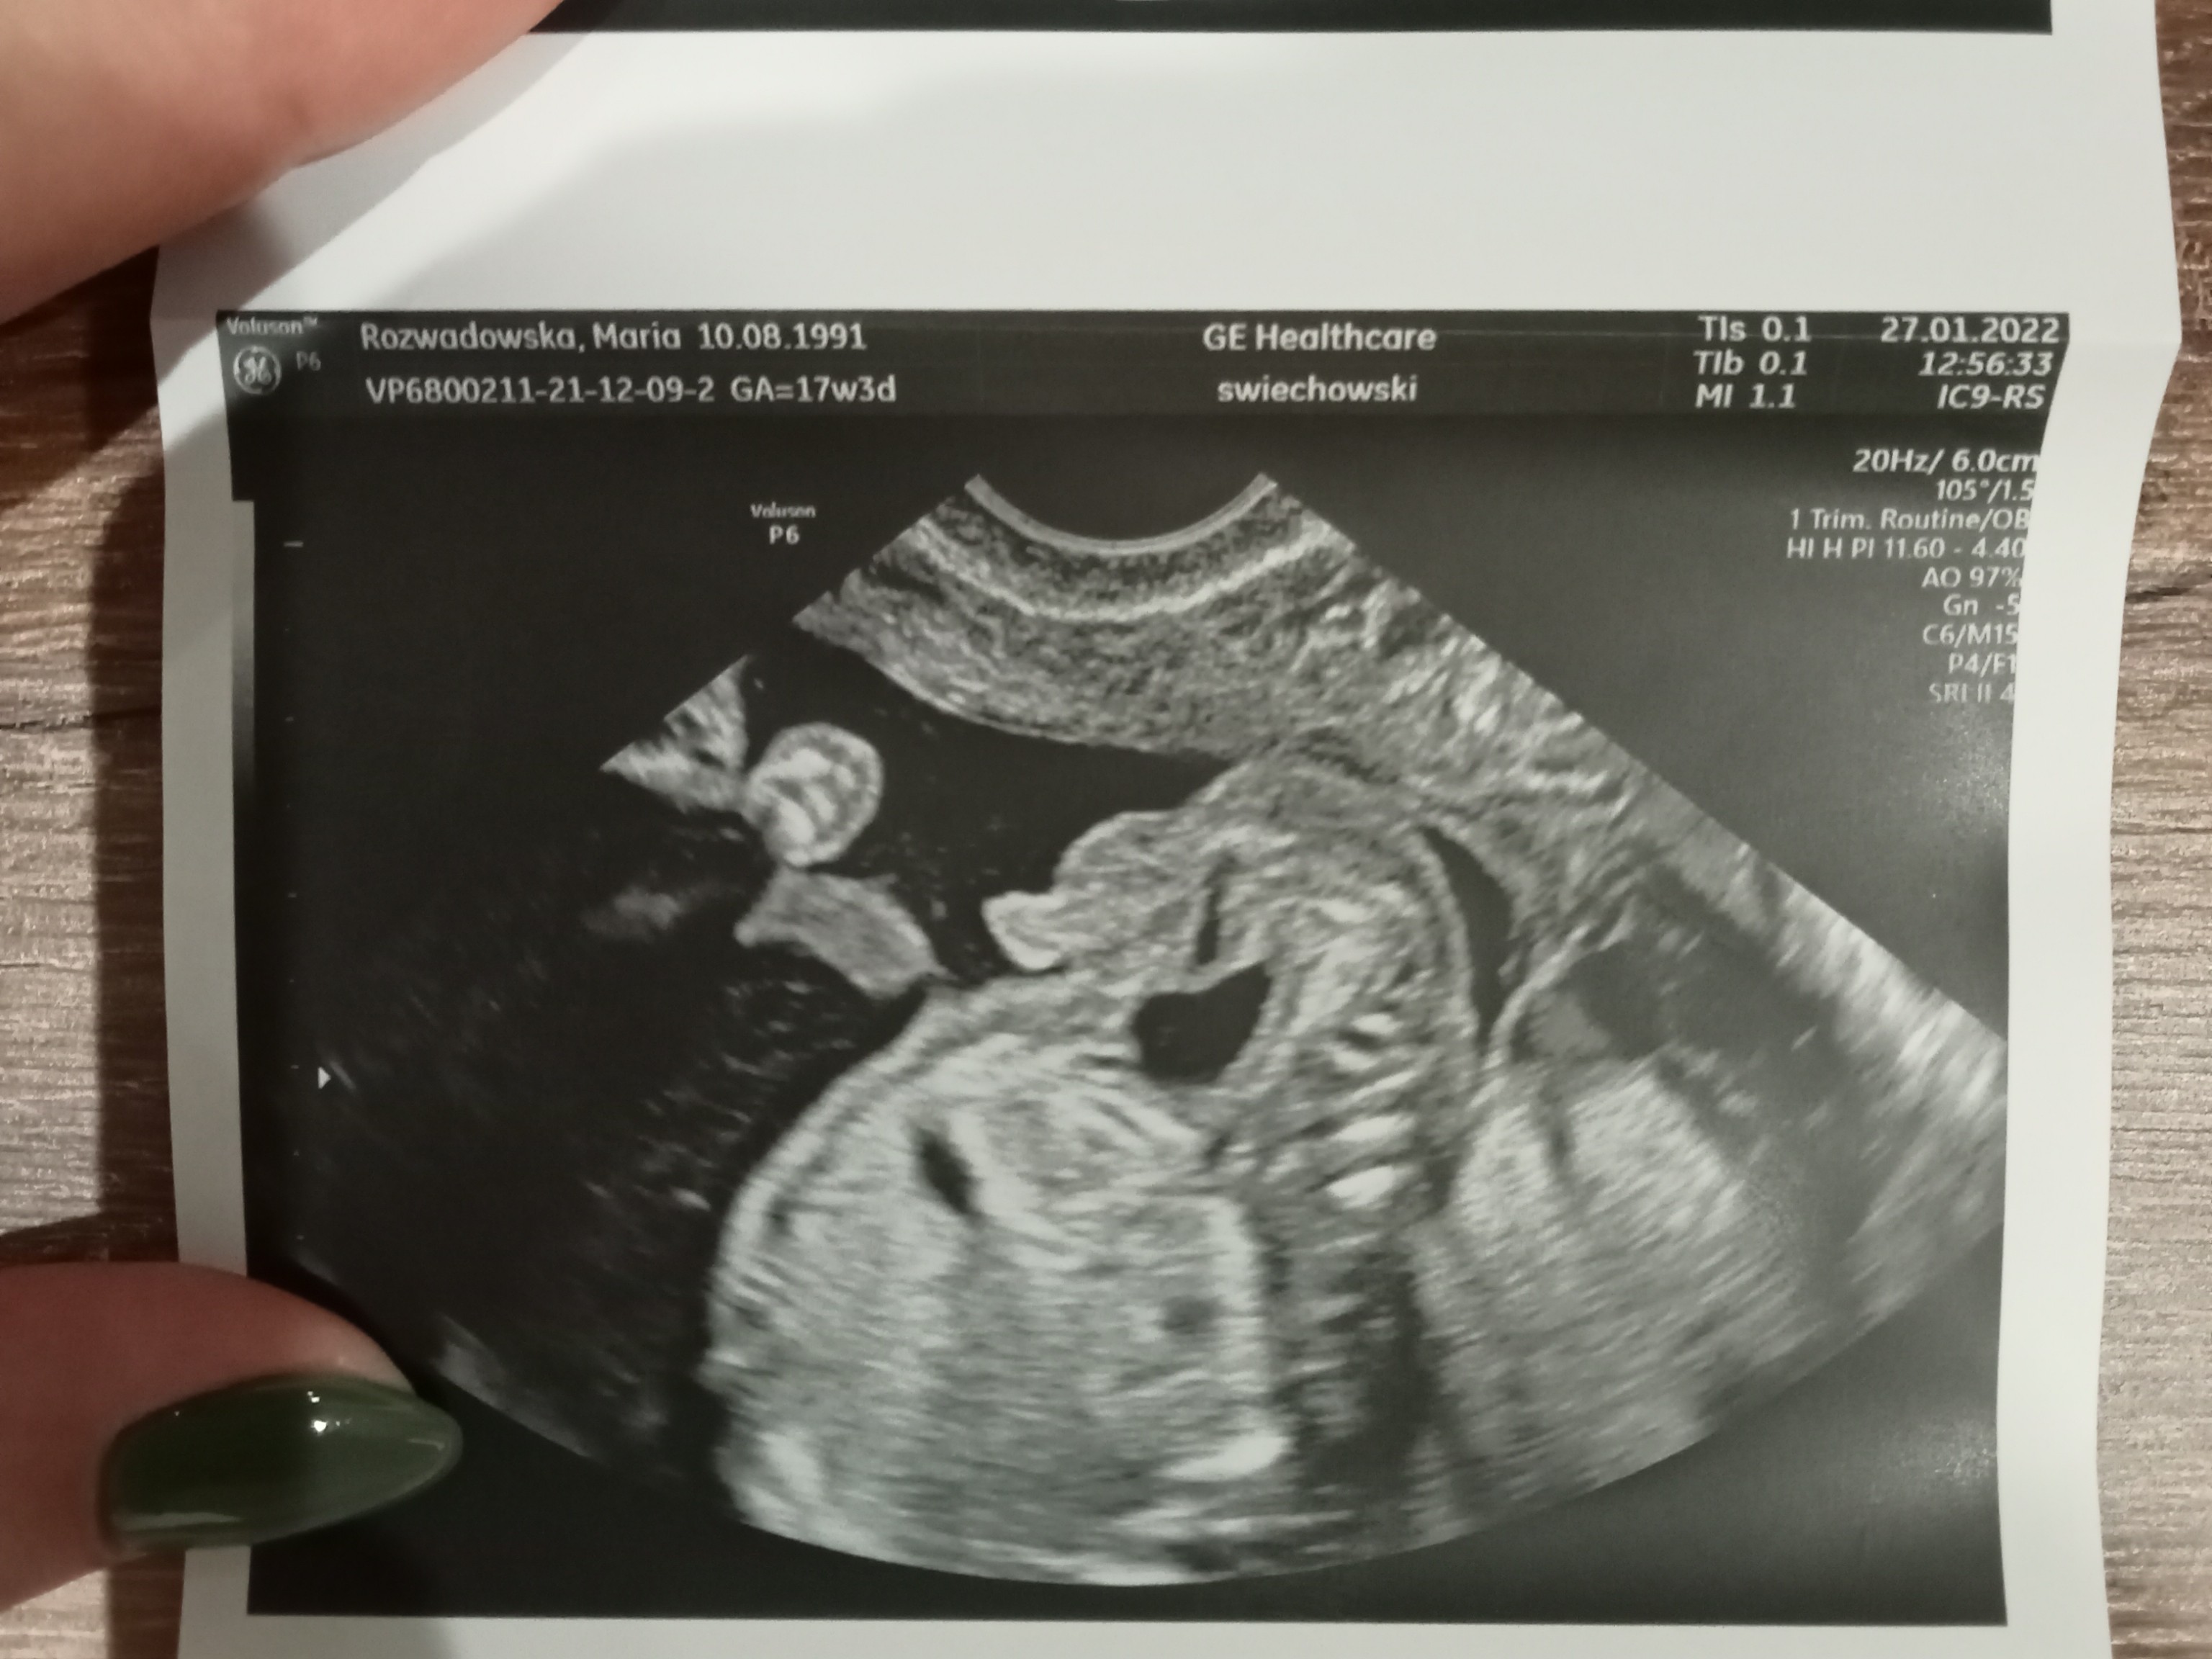

Siusiak czy pępowina?

Hej, w 12 tyg ciąży na prenatalnych sugerowano mi, że to dziewczynka, natomiast przy kolejnym usg w 18 tyg lekarz prowadząca powiedziała, że chłopiec. Co myślicie?

W 16 , że chłopak też widziałam siusiaka, a w 20 ponownie że dziewczynka , połówkowe to potwierdzały( więc tamten siusiak był pępowiną) za niedługo będziesz miała połówkowe więc poproś o 4d będziesz miała pewność ☺️☺️